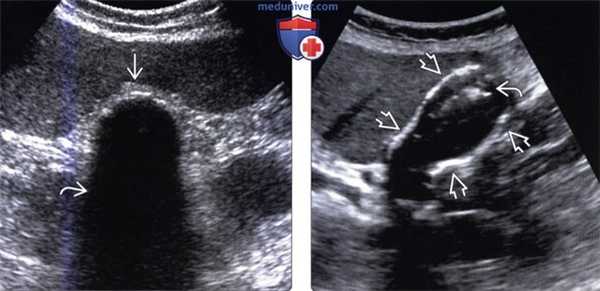

(Слева) На поперечной трансабдоминальной сонограмме в ямке желчного пузыря визуализируется эхогенная структура изогнутой формы с акустической тенью — изменения, характерные для «фарфорового» желчного пузыря.

(Справа) На сонограмме визуализируется стенка желчного пузыря с диффузно повышенной эхогенностью и объемное образование в области его дна. Задняя стенка желчного пузыря различима, в отличие от эмфизематозного холецистита или множественных камней, заполняющих желчный пузырь. При патоморфологическом исследовании были обнаружены интрамуральные кальцинаты, признаки хронического холецистита и аденокарциномы желчного пузыря.